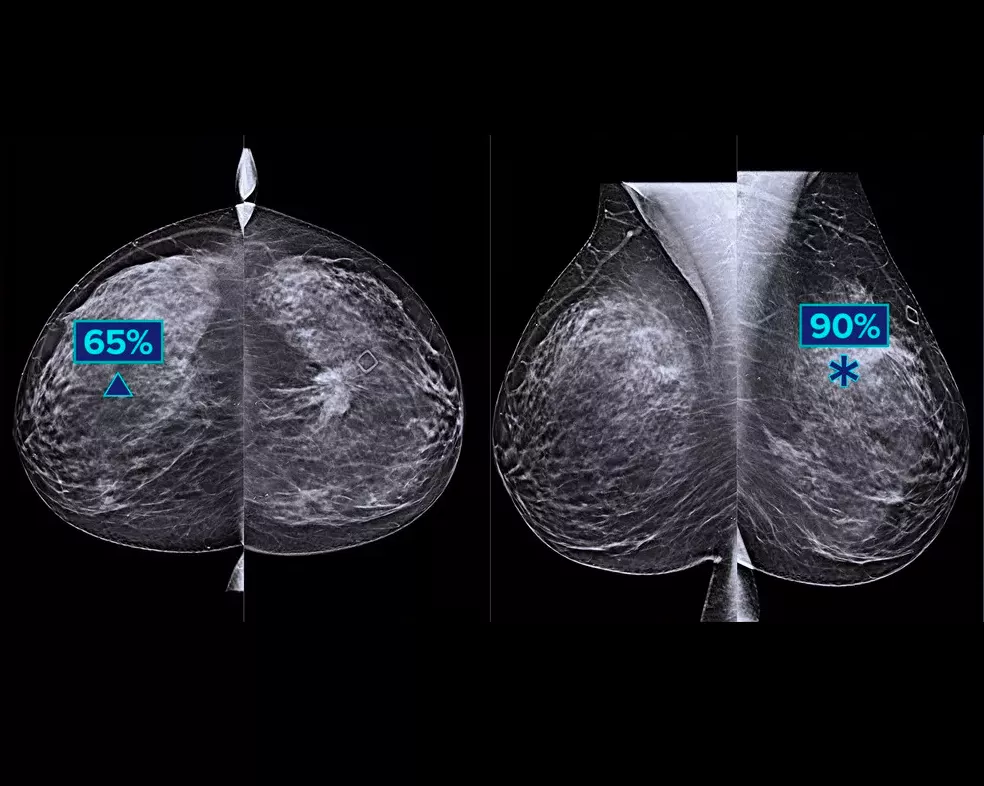

Un algorithme d’intelligence artificielle conçu pour aider les radiologues à effectuer des diagnostics et à détecter un cancer du sein1-3 à partir d’images de tomosynthèse obtenues à l’aide du système Hologic Dimensions Mammography®. L’algorithme localise les lésions susceptibles de représenter un cancer du sein en étudiant chaque coupe de l’ensemble des images de tomosynthèse. Les zones suspectes sont mises en évidence sur le poste de travail du radiologue pour permettre une lecture simultanée et aider à l’interprétation.

L’étude montre une amélioration de +9 % de la sensibilité observée du lecteur pour les cas de cancer.1.2 Fonctionne avec des images de tomosynthèse standard et haute résolution ; superposition sur des images 3DQuorum SmartSlices et 2D synthétiques.

L’algorithme recherche les 3 principaux groupes de lésions suspectes : calcifications, masses, densités et distorsions ; ainsi que les combinaisons de ces lésions. Les données de sortie peuvent varier selon les postes de travail.

Usage préconisé : Genius AI Detection est un logiciel de détection et de diagnostic assisté par onlinateur (CADe/CADx) destiné à être utilisé avec des systèmes de tomosynthèse mammaire numérique (DBT) compatibles pour identifier et marquer des régions d'intérêt y compris les densités de tissus mous (masses, distorsions architecturales et asymétries) et les calcifications, lors de la lecture des examens de DBT à partir de systèmes de DBT compatibles, et pour fournir des scores de confiance qui permettent d'évaluer la certitude des résultats et un score du cas. Le dispositif vise à faciliter l'interprétation des examens de tomosynthèse mammaire numérique de manière simultanée lorsque le médecin interprète confirme ou infirme les résultats lors de la lecture de l'examen.